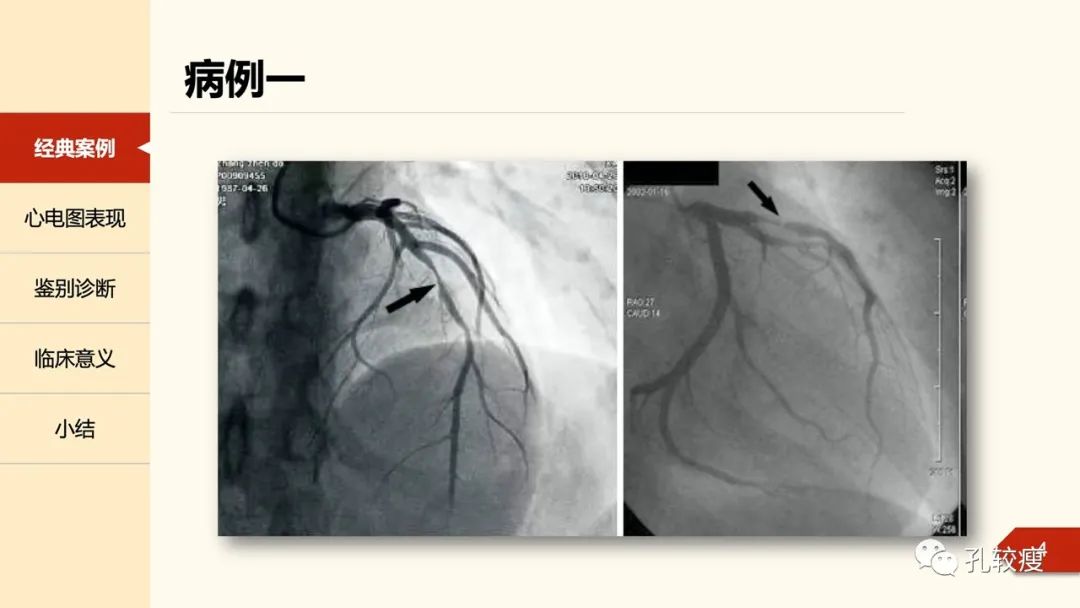

早在1955年,Pruitt等在Circulation上报道了不稳定型心绞痛患者胸前导联心电图T波双支对称性深倒置,并逐渐恢复直立的病例,其不伴QRS波及ST段改变。。

1979年, Gerson及其同事又描述36例运动后诱发的U波倒置的病案,实际上,这些表现类似于Wellens综合征的第二个亚型。当时人们以为双向T波的倒置部分为U波;这部分患者在冠脉检查中均提示存在前降支近端的狭窄。时隔一年,Gerson在文章中再次描述了部分患者在静息状态下仍可出现此类心电图改变,与心绞痛发作出现并不平行。